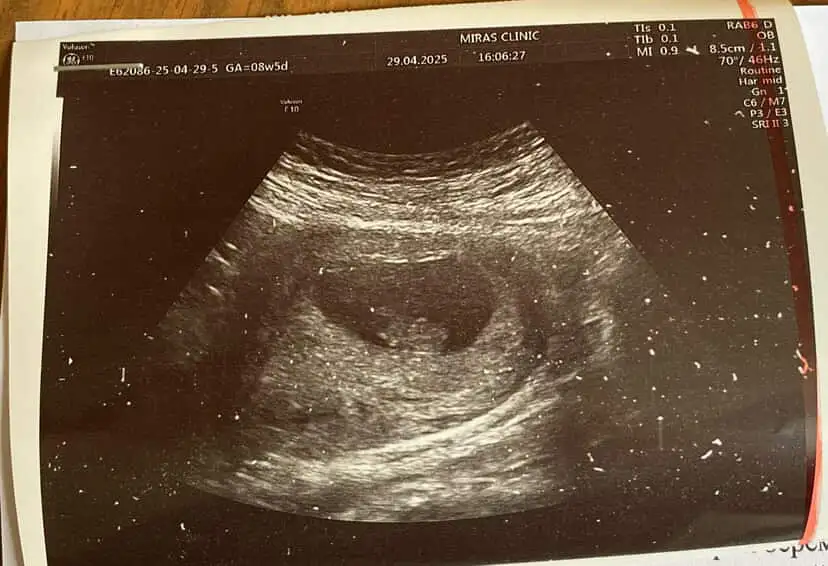

8+3 karından ultrasonla çekildi cinsiyet tahmini yapabilecek var mı acaba

6 haftalık ve 8 haftalik yorumunuzu banada yapabilir misiniz